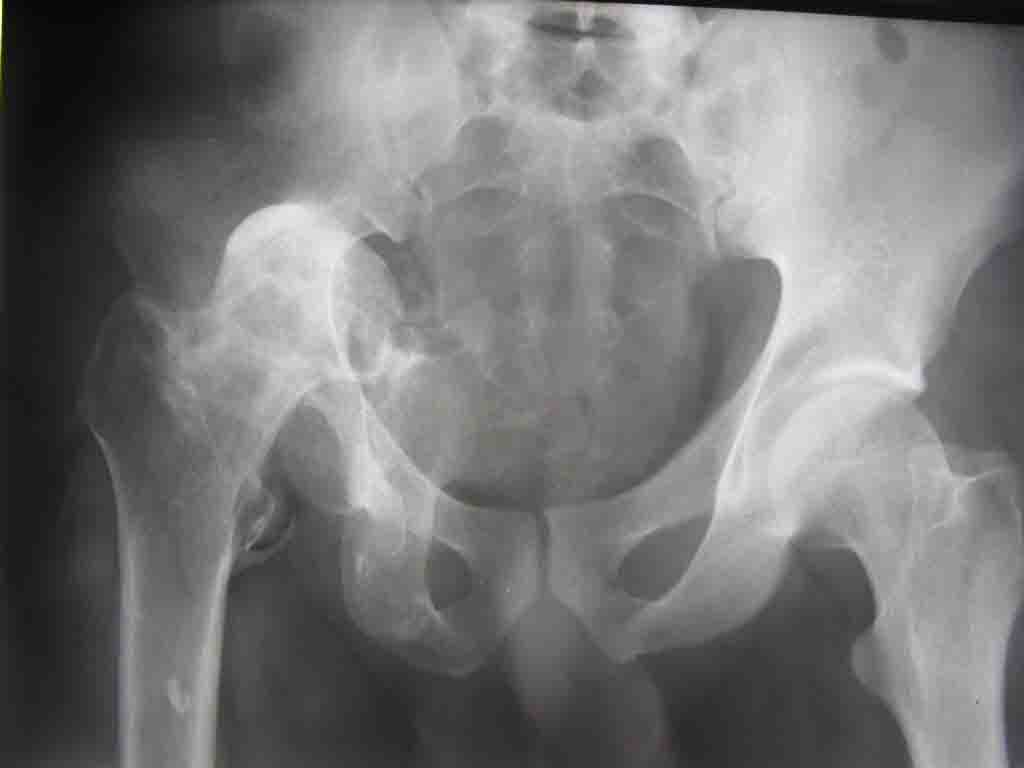

Уважаемые коллеги! На консультацию пришел молодой человек 23 лет с застарелым задним вывихомбедра. После травмы прошло 2,5 ГОДА.

Были переломы бедра и голени на этой же стороне, которые благополучно срослись после остеосинтеза. вывих бедра был пропущен. В настоящее время ходит без дополнительной опоры, есстественно, сильно хромает, выражен болевой синдром, парез седалищного нерва. Сформировался неоартроз в подвздошной области, виден неправильно сросшийся перелом задней колонны, сгибание в суставе до 80.

1.Большой костный посттравматический дефект вертлужной впадины. Поэтому необходима КТ для четкого планирования операции. При наличии контакта чашки с вертлужной впадиной на 55-60%% недопокрытие компенсируется за счет костной аутопластики собственной удаленной головкой (фиксация головки минимум 2-я винтами). Если недопокрытие большое, или не удается установить чашку, то можно установить кольцо Мюллера, опять же с костной пластикой.

Схематично можно сказать так - если есть контакт с 60% и более ВВ, то этого достаточно для последующей биологической фиксации чашки. Опять же НО, мы стараемся "подрыться" фрезами так, что бы был приемлимый упор чашки, а фиксация аутотрансплантата головки была прочной без каких либо дефектов и зазоров.